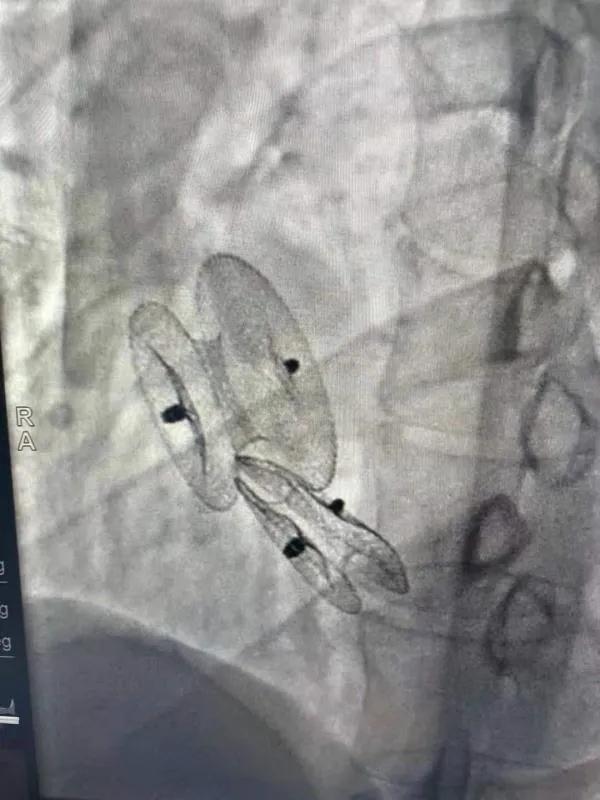

先天性心臟病房間隔缺損呈多孔型怎么辦?患者并非只能選擇開胸手術(shù)。近日,西安國際醫(yī)學(xué)中心醫(yī)院心臟病醫(yī)院成功開展一例雙孔房間隔缺損雙傘介入封堵術(shù)。

房間隔缺損是先天性心臟病的一種,介入手術(shù)相較于傳統(tǒng)的外科手術(shù)損傷小,風(fēng)險(xiǎn)相對較低,術(shù)后恢復(fù)快。一般的房間隔缺損多呈單孔,封堵難度較小,而雙孔房間隔的封堵難度大大增加,至今僅有國內(nèi)頂尖的封堵專家成功完成了數(shù)例而已。

患者是位27歲的年輕女性,經(jīng)常感到心慌,心臟超聲發(fā)現(xiàn)房間隔缺損,并且房間隔缺損呈雙孔型,大的約14mm,小的約9mm,兩個缺損間相隔較遠(yuǎn),介入封堵難度非常大。

在詳細(xì)了解患者病情,仔細(xì)閱讀患者影像資料后,曾廣偉主任已經(jīng)有了清晰的手術(shù)策略。在精心的準(zhǔn)備和團(tuán)隊(duì)的配合下,曾主任順利的利用兩個封堵器對房缺進(jìn)行了封堵。